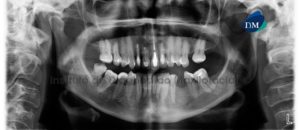

Paciente femenino de 27 años de sexo femenino acude al Instituto de Diagnóstico Maxilofacial para evaluación preoperatoria de cirugía ortognática. A la evaluación de la